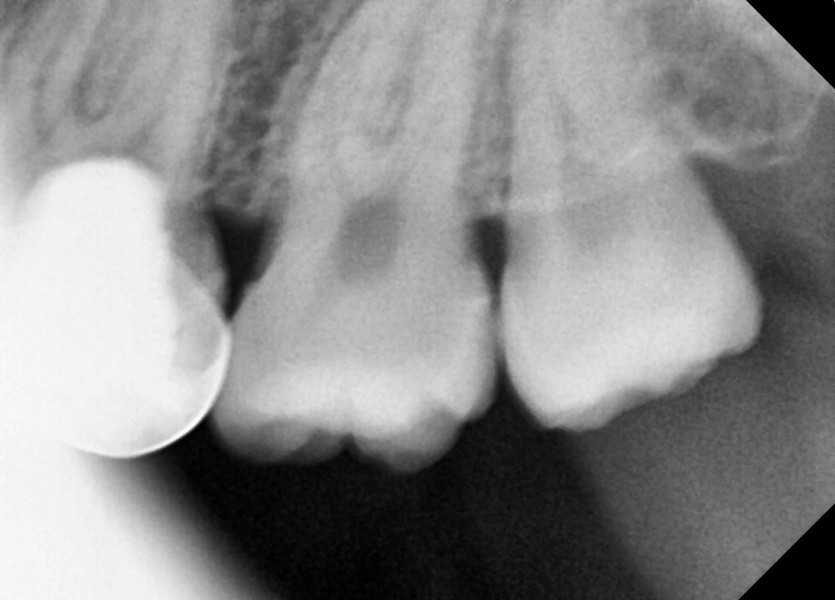

#18,28,38,48 사랑니 발치

구강 외과 전문의가 당일 발치했습니다.